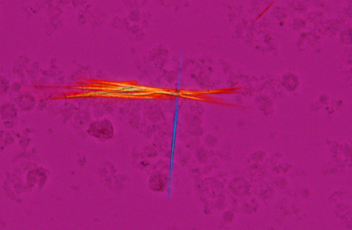

灵敏的彩色偏光

这使得通过改变干涉色形成生物体内部尿酸结晶的鉴定。它是理想的痛风和假性痛风的检测。

*有两种类型的分析仪可供选择:中间管式和消防水枪滑盖式。

钠尿酸盐结晶,灵敏的彩色偏光,CFI Plan Fluor 40X,图片来自日本大学板桥医院临床检验科